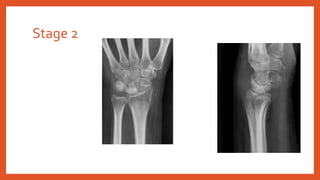

• Stage 2: Lunate sclerosis

Stage 2